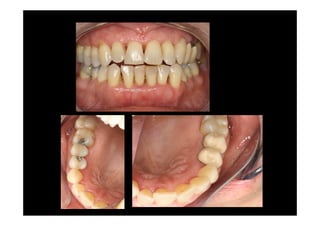

Prosthodontic rehabilitácion

Modified widman flap